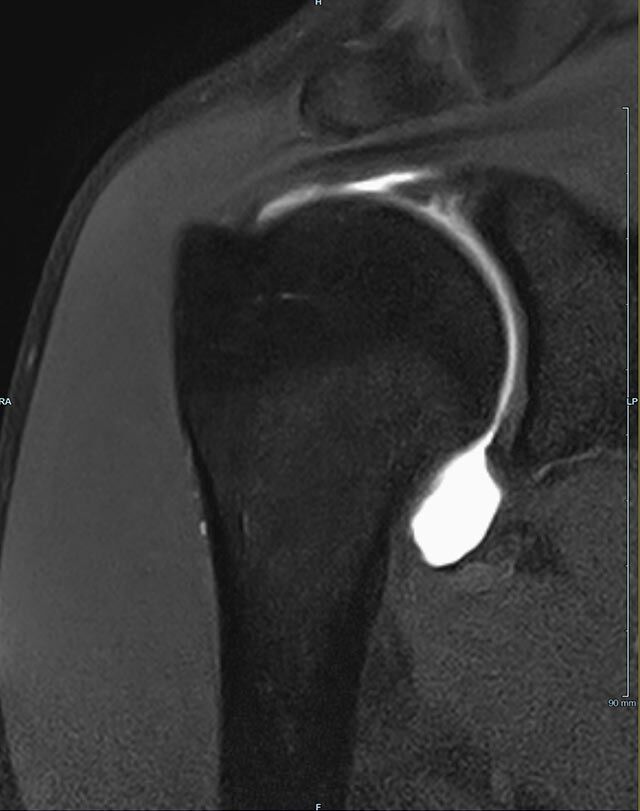

Gelenke

• Beurteilung von Knochen, Bändern und anderen Weichteilstrukturen der Gelenke nach Unfall.

• Impingement-Symptomatik

Arthrographie

• MR-Arthrographie – nach örtlicher Betäubung und gründlicher Desinfektion der Haut wird unter Lagekontrolle mit Röntgen-Durchleuchtung eine kleine Nadel in den Gelenkraum positoniert und darüber ein MR-taugliches Kontrastmittel in den Gelenkraum gespritzt. Danach wird die Nadel entfernt. Anschließend erfolgt die MRT des Gelenkes. Diese Methode stellt kleine anatomische Strukturen des Gelenkraumes verbessert dar, z.B. zur Therapieplanung vor Arthroskopie bei Sportverletzungen der Schulter oder Gelenkinstabilität.